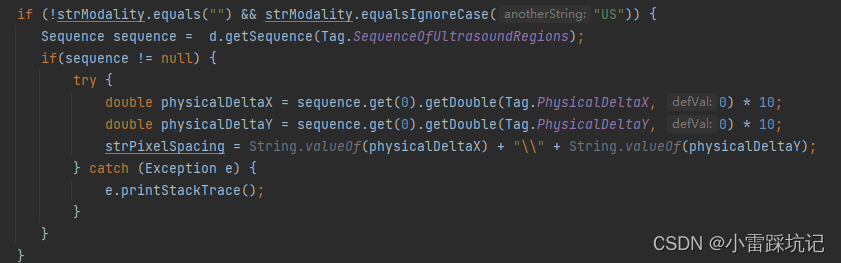

特别注意一下这个 PhysicalDeltaX ,PhysicalDeltaY 值需要同时 *10,才是最终像素

我是用的java dcm4che 解析的,这个时候直接解析对应的Tga值,是解析不出来的.

先解析对应的sequence值,然后在sequenc值里面再解析对应的tag值